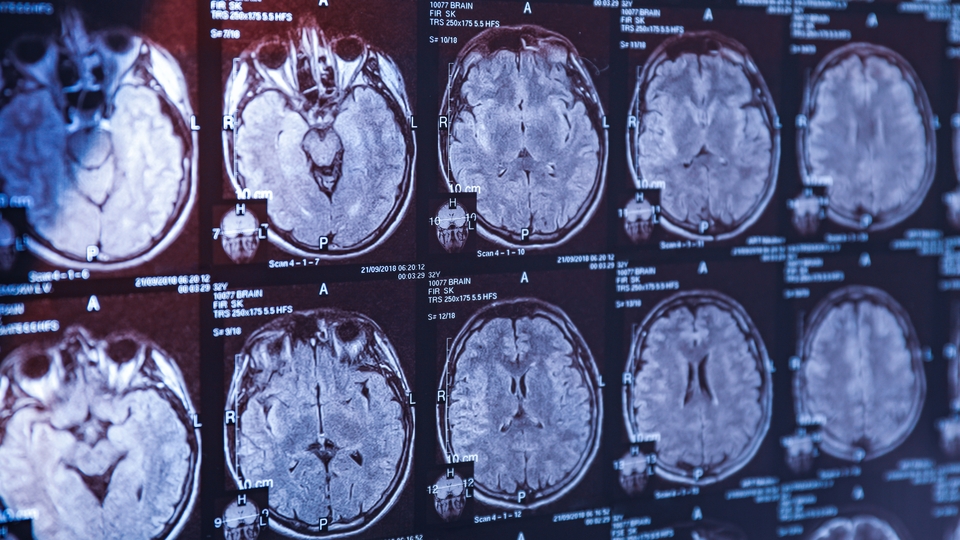

Alzheimer ile mücadelede artık tanı için bir kan testi yeterli. Özellikle ileri yaştaki bireyler için büyük bir endişe kaynağı olan Alzheimer hastalığının teşhisinde çığır açan bir gelişme yaşandı. Amerikan Gıda ve İlaç Dairesi'nin (FDA) onayladığı yeni kan testi, milyonlarca insana umut ışığı oldu. Nöroloji Uzmanı Prof. Dr. Lütfü Hanoğlu, bu tarihi adımı şu sözlerle değerlendirdi: "Artık hastalığın biyolojik tanısını kan yoluyla koymak mümkün. Bu da erken teşhis ve etkili tedaviler için çok büyük bir avantaj sağlıyor."

Prof. Dr. Hanoğlu, Alzheimer’ın bugüne kadar daha çok klinik semptomlara göre tanılandığını, ancak son yıllarda biyolojik belirteçlerle tanının desteklenmeye başlandığını hatırlattı. "Daha önce belden sıvı alma yöntemiyle yapılan biyobelirteç testleri artık yerini çok daha pratik bir yöntem olan kan testine bırakıyor. Kan yoluyla yapılan bu testler sayesinde hastalığın erken döneminde tanı koymak mümkün hale geliyor" ifadelerini kullandı.